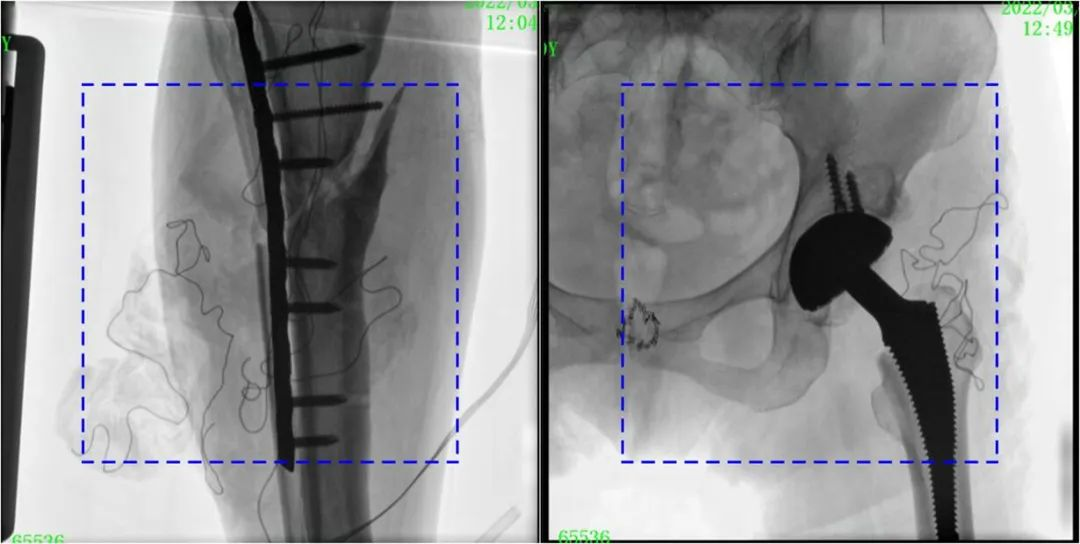

與傳統(tǒng)的21CM×21CM成像尺寸相比,普愛醫(yī)療大平板一體式C形臂具有30CM×30CM更大成像尺寸,能夠一次成像5.5節(jié)椎體,呈現(xiàn)更全面的影像信息,即便是手術經(jīng)驗不豐富的年輕醫(yī)生也能通過圖像迅速判斷椎體節(jié)段、定位手術部位,避免因為視野不足而造成的多次定位、反復曝光,提高效率的同時避免過量攝入輻射。

普愛醫(yī)療大平板一體式C形臂圖像與傳統(tǒng)圖像對比(藍色虛線內(nèi)為傳統(tǒng)21CM×21CM平板的成像區(qū)域)